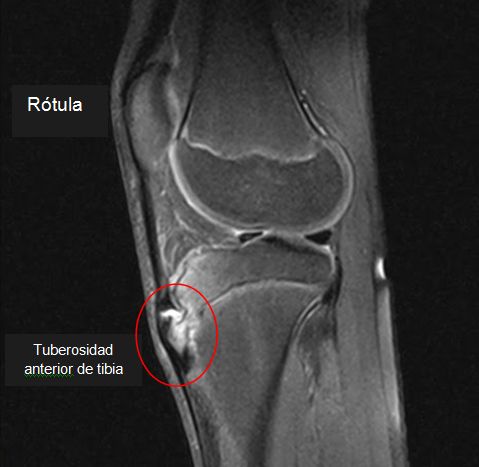

Hallazgos de la RM incluyen el engrosamiento y edema del tendón rotuliano distal, la bolsa infrarrotuliana distendida por fluido, el edema del tejido blando circundante, y edema de médula ósea subyacente a la tuberosidad tibial.

Radiografías de la rodilla pueden mostrar la fragmentación del tubérculo tibial, hinchazón de los tejidos blandos, y la obliteración del ángulo inferior de la almohadilla de grasa de Hoffa.

Es una entidad que produce dolor en la región anterior de la rodilla  (tuberosidad tibial), conocida como enfermedad de Osgood-Schlatter (EOS).  La condición, es un resultado de una tracción que ocurre en la tuberosidad tibial a causa del tirón del grupo muscular de los cuádriceps a través del tendón de la rótula.

Actualmente es ampliamente aceptado que la EOS es una tracción del tubérculo tibial debido a esfuerzos repetitivos, y avulsión crónica del centro de osificación secundario de la tuberosidad tibial. El esfuerzo repetitivo es un fuerte tirón del músculo cuádriceps producida durante las actividades deportivas. La avulsión de la tuberosidad tibial puede ocurrir en la fase pre-osificación, o con el centro de osificación secundaria ya osificado.

Una vez que el hueso o cartílago se  separa, sigue creciendo, y osificando  agrandándose. El área intermedia puede llegar a ser fibroso, la creación de una falta de unión localizada (huesecillo persistente separado), o puede mostrar la unión ósea completa con agrandamiento leve de la tuberosidad tibial.